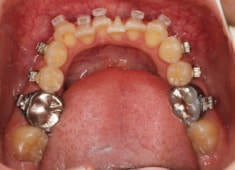

治療開始時